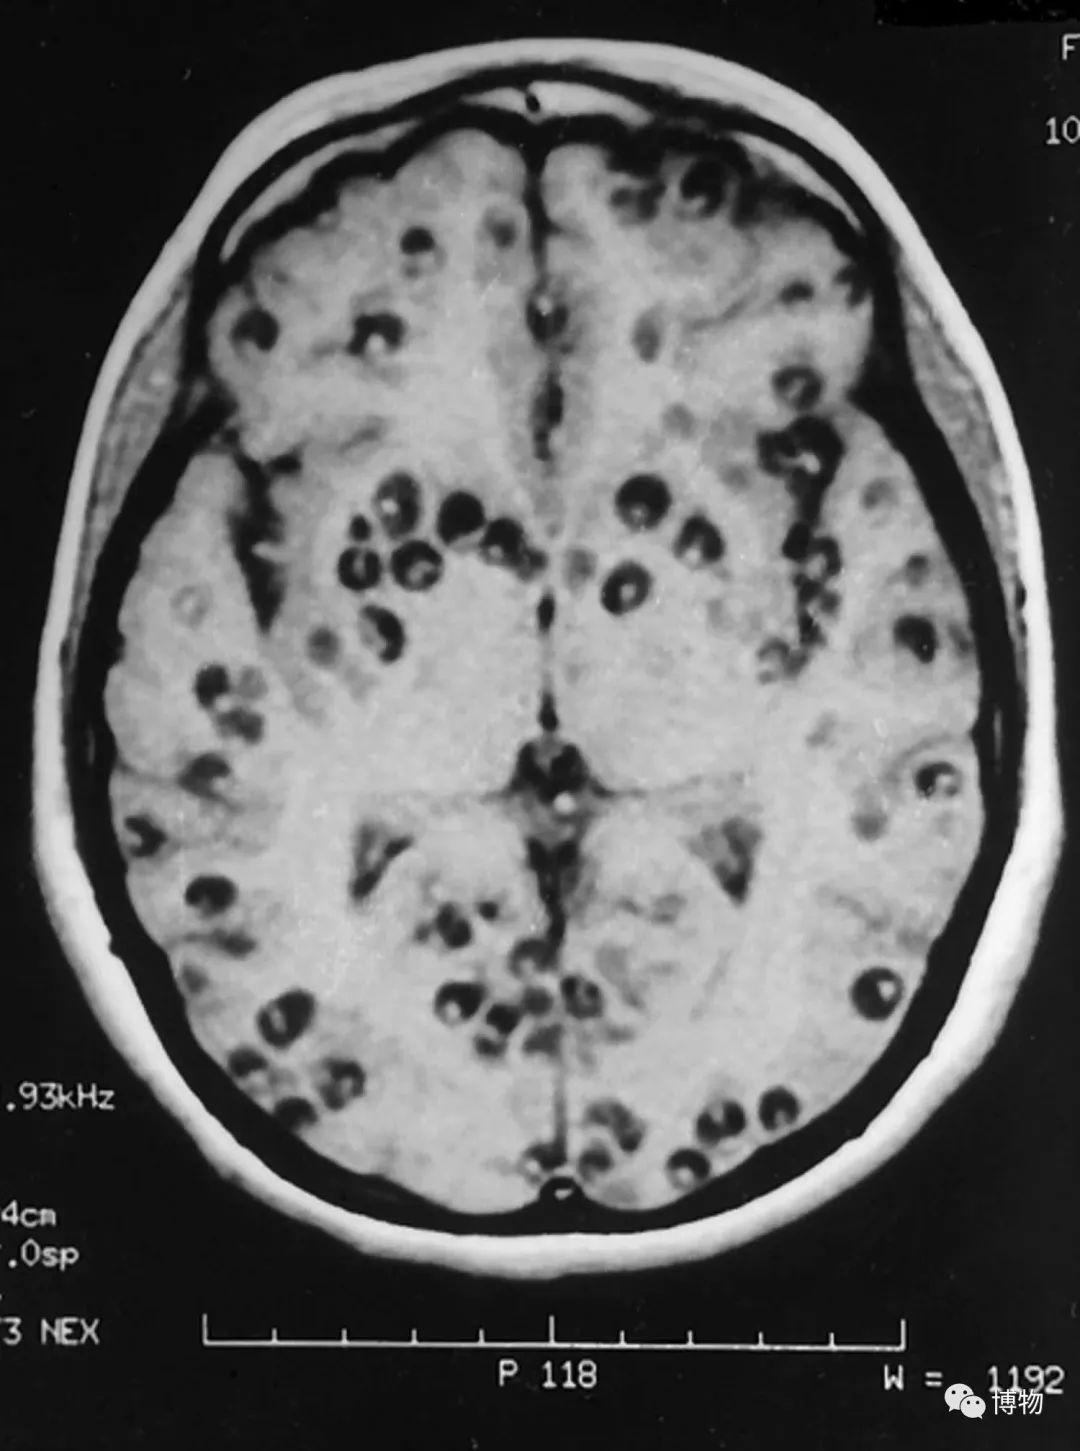

影像学病例分析:全身播散性囊虫病 3 例